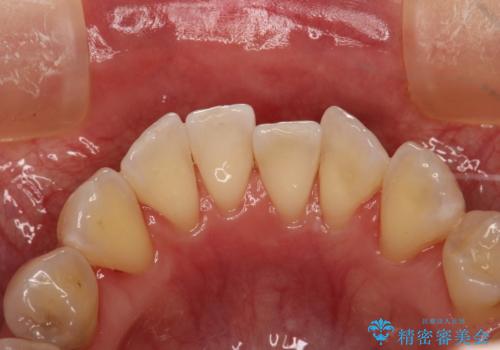

PMTC30分コース(保険外治療)を行いました。かなり久しぶりの歯科医院へ来院とのことで、プラーク(歯垢)・歯石・ステイン(着色)が付着していました。汚れを除去し、本来のご自身の歯質にすることでなにか異常があった際に発見しやすくなります。

PMTCで汚れを除去することは、虫歯や歯周病・口臭予防に効果的です。

また、今回はクリーニング後に、何か所か虫歯や治療途中のままの部分が発見されました。今後は定期的なメンテナンス・クリーニングと併用しながら虫歯の治療を行っていく予定です。